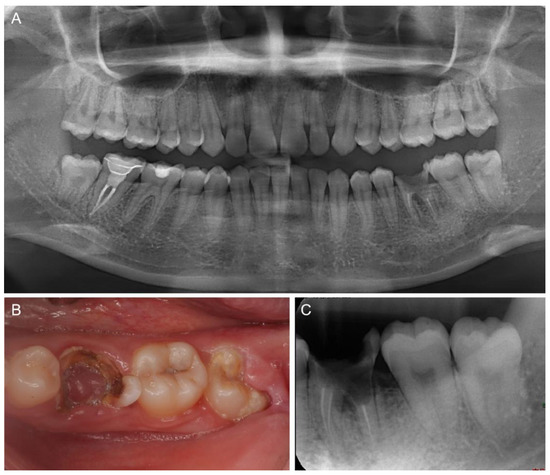

2. Case Report

3. Results